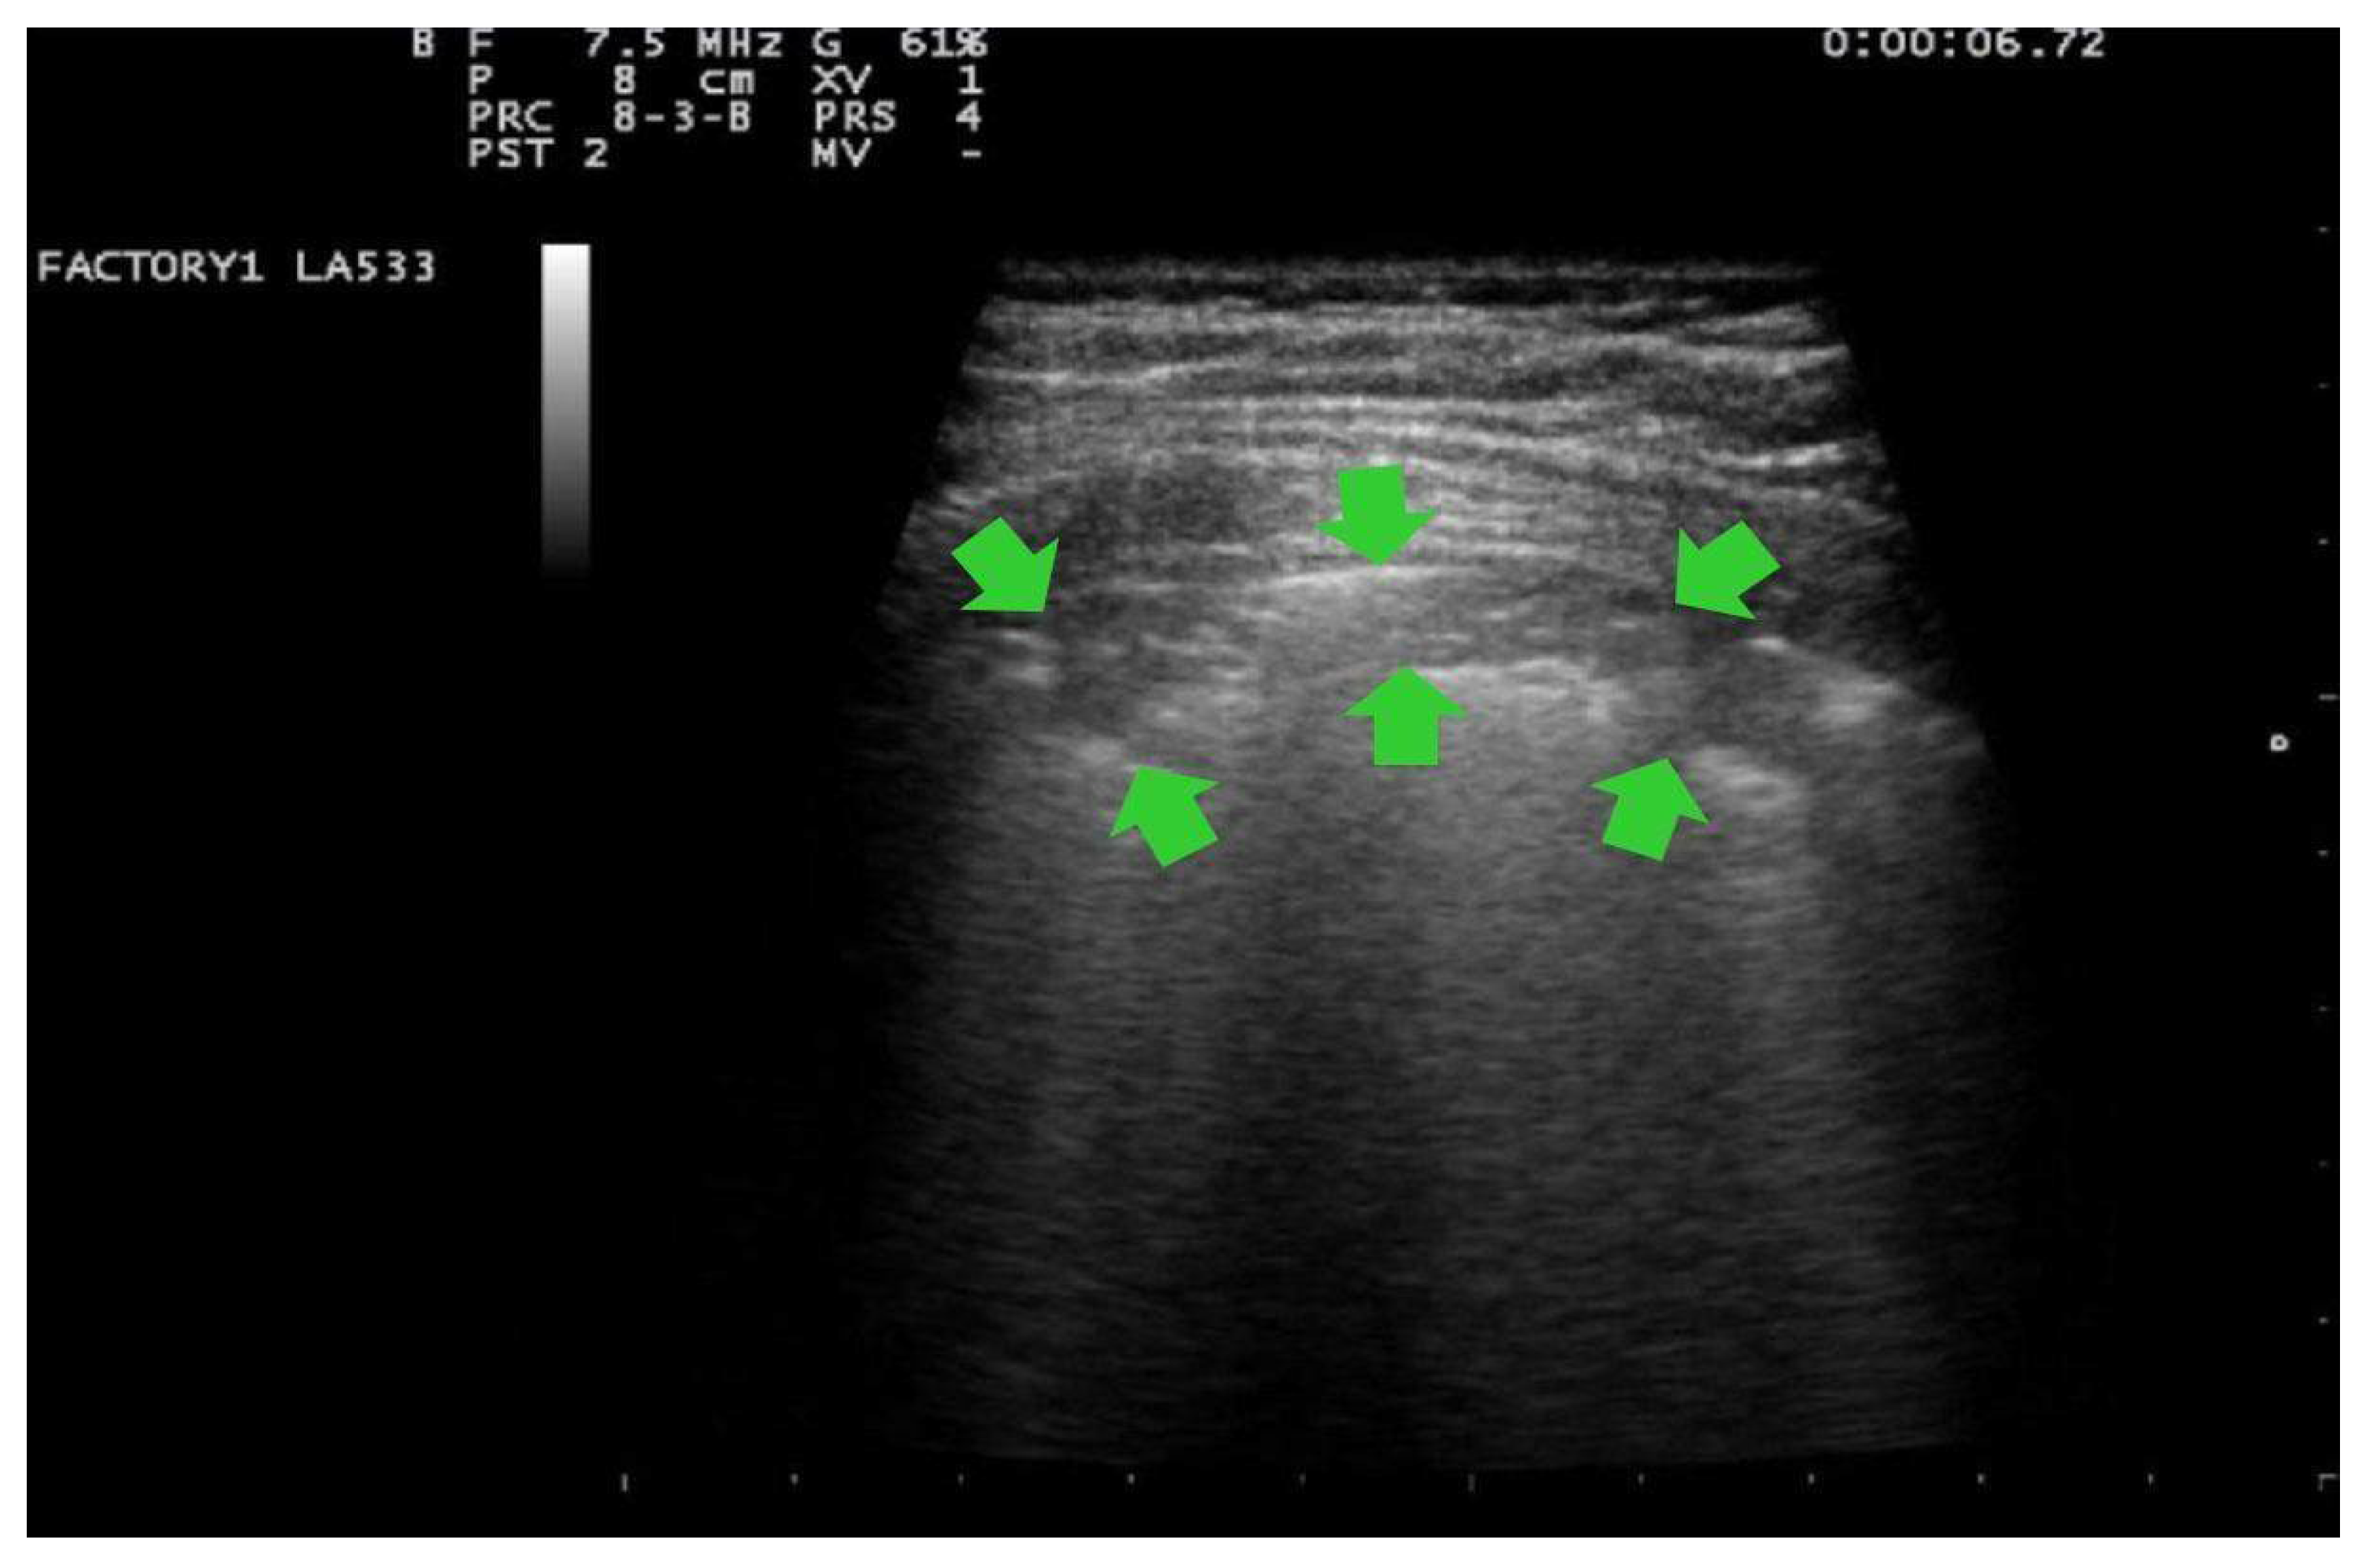

- Score 0:

- predominant A-lines or <3 separated B-lines. (Figure 1)